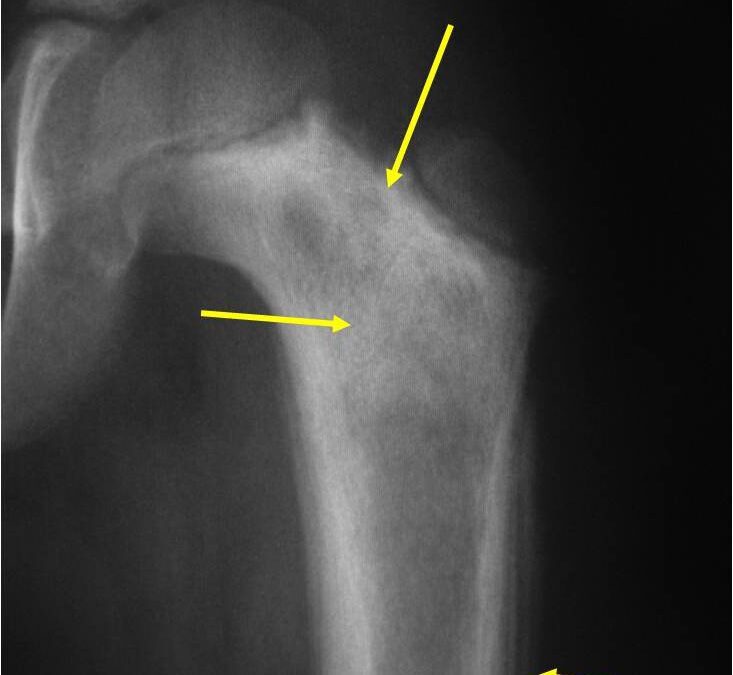

A dedifferentiated chondrosarcoma is a highly aggressive cancerous cartilage tumor or neoplasm. If this tumor is not removed, it will bore into the bone. This may lead to bone breaking, also known as a pathological fracture. It has a very high risk of spreading to other parts of the body.

A Conventional Chondrosarcoma is a cancerous bone tumor. It consists of cartilage located within the bone. It is a cancerous tumor, and can lead to bone destruction. It is a slow growing tumor that will not spread to other parts of the body in most cases.